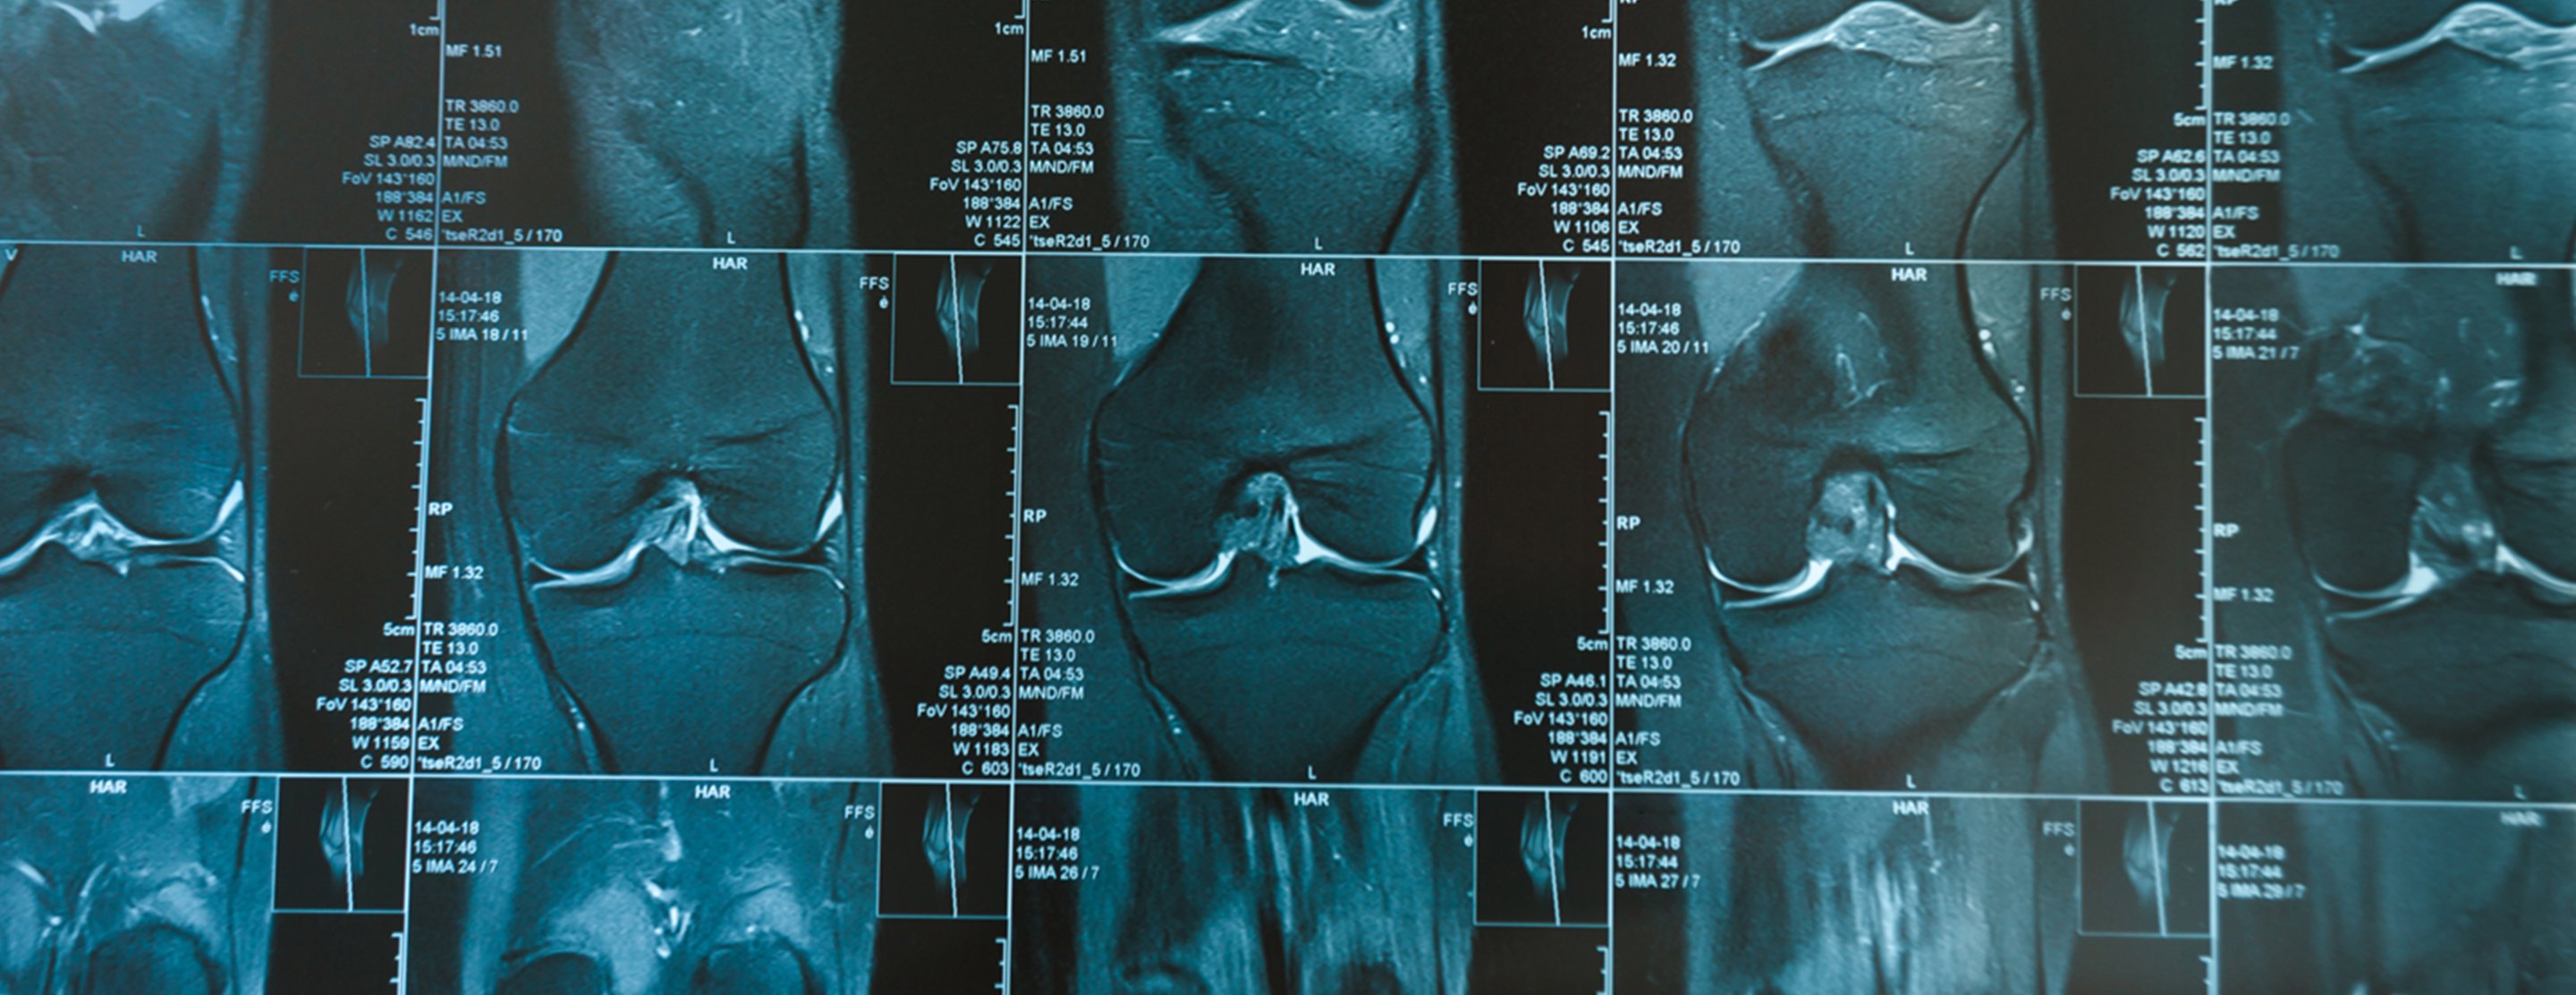

Knee MRI scan

A knee MRI (magnetic resonance imaging) scan uses energy from strong magnets to create pictures of the knee joint and muscles and tissues.

An MRI does not use radiation (x-rays). Single MRI images are called slices. The images can be stored on a computer or printed on film. One exam produces many images.